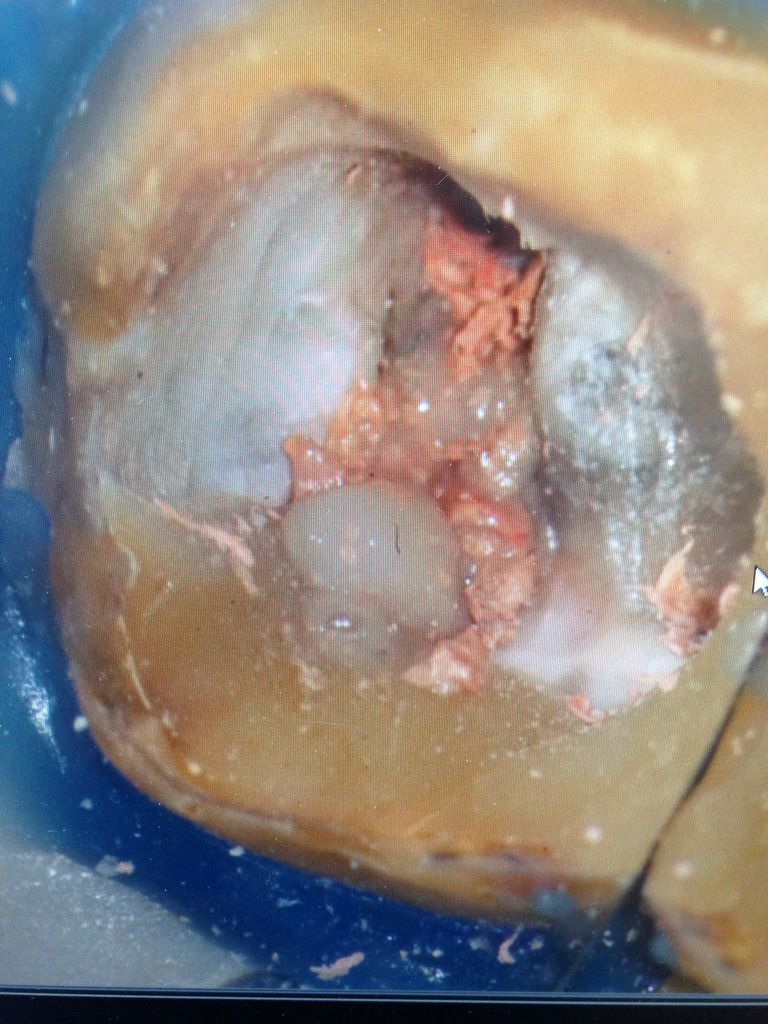

神経の管にはレントゲンや手術用顕微鏡でも見えない細いクダがたくさんあります。

歯科医が消毒できるのは、せいぜいレントゲンで見える本管、木の幹のような部分だけです。

細く分かれた枝や葉にまで入り込んだ最近は取り除けません。

消毒薬をしみ込ませるのが、せいぜいできる事なんです。